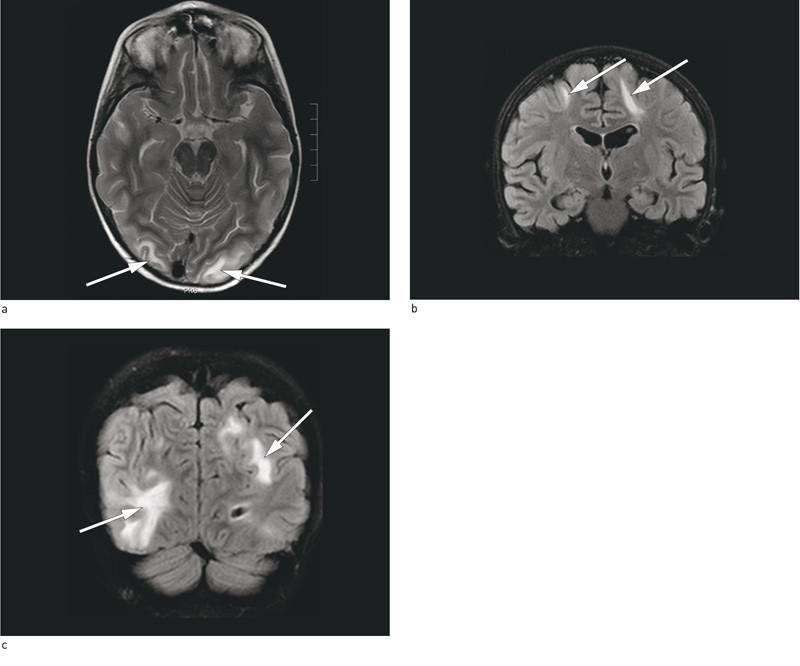

Det ble gjort ny MR caput med kontrast (fig 1), og det ble beskrevet subkortikalt ødem oksipitalt bilateralt og parietalt venstre side samt mindre områder i vannskilleområdet frontalt. Områdene hadde økt diffusjon. Hemoserie viste multiple små områder oksipitalt, tolket som små blødninger. Det var imidlertid gode plassforhold. Funnene ble beskrevet som forenlig med PRES-diagnosen. Ved ny gjennomgang av de tidligere MR-bildene kunne også de gi mistanke om det samme.

Det klassiske bildet er symmetrisk ødem i hvit substans baktil i hjernehemisfærene, med parietal- eller oksipitallappene affisert i 98 % av tilfellene (9). Samtidig er det vanlig med affeksjon av andre deler av hjernen: frontallappene er rapportert å være affisert i 68 % av tilfellene, temporallappene i 40 % og cerebellærhemisfærene i 30 %, og mer enn en firedel av lesjonene er asymmetriske (9). Ettersom de tidlige forandringene kan være subtile, bør man beskrive den kliniske mistanken på rekvisjonen, slik at radiologen kan se spesielt etter disse forandringene.